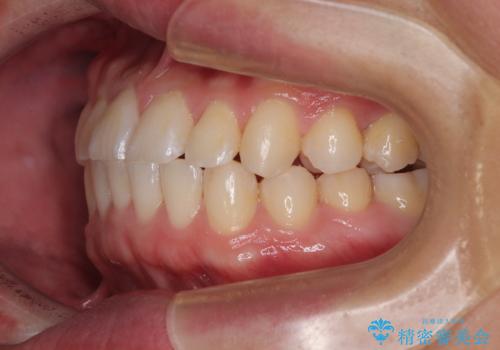

**前歯のデコボコ(叢生)**が整い、歯列全体が美しく改善

シザーズバイトの奥歯も正常なかみ合わせに改善

捻転歯も回転が修正され、全体的に清掃性・咀嚼効率が向上

患者様にも「大人になってから矯正を始めることに不安もありましたが、思っていたよりも短期間で治療が終わって本当にうれしいです。前歯のガタガタも気にならなくなり、笑うことに自信が持てるようになりました!」と喜んでいただけました。